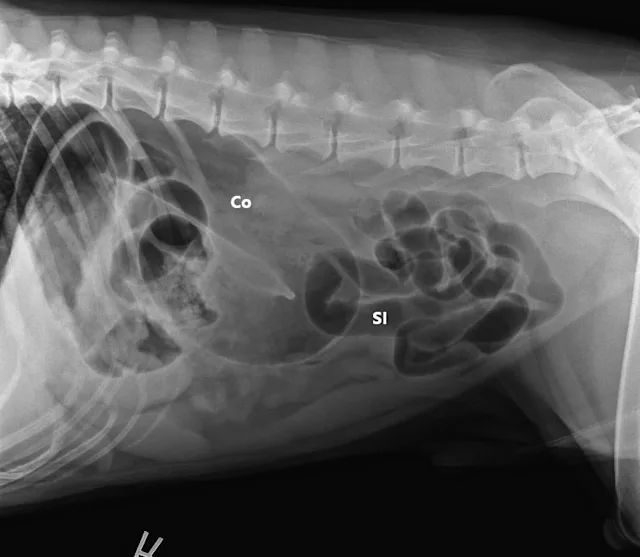

Three-view abdominal radiographs revealed a single bowel loop markedly dilated with gas and amorphous material in the cranial abdomen thought to represent the colon due to its unusual position (ie, could not be tracked from caudal to cranial aspect on lateral radiograph; Figure 1). The small intestines were displaced caudally with no evidence of ileus (ie, gas filled but normal and uniform in diameter), and the descending colon was not fully visualized.

FIGURE 1A

Right lateral (A), left lateral (B), and ventrodorsal (C) abdominal radiographs demonstrating marked dilation of a single bowel loop with gas and amorphous material in the right cranial abdomen, suspected to be the colon (arrows). Caudal displacement of the small intestines (SI) can also be seen. The descending colon (Co) is poorly visualized.